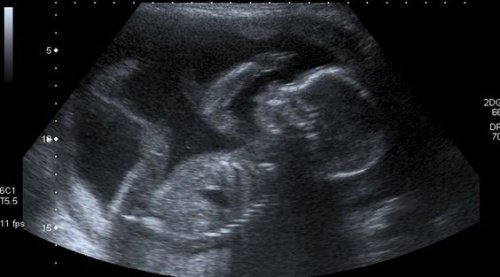

Kobieta zdaje sobie sprawę, że jest matką podczas pierwszego USG. Nie potrafi wtedy powstrzymać łez wzruszenia. Słysząc gwałtowne bicie serduszka swojego dziecka jej własne zaczyna bić równie szybko. Przytłacza ją ogromne szczęście wywołane pierwszym kontaktem ze swoim nienarodzonym dzieckiem. Nowym członkiem jej rodziny.

Niespokojna matka marzy o dniu w którym po raz pierwszy będzie mogła trzymać w ramionach swoje małe słońce. Wie, że są związani na całe życie. Każde USG, każdy mały ruch, stają się kamieniami milowymi w życiu wszystkich matek.

Przez następne dziewięć miesięcy będzie musiała zadowolić się rozmytymi obrazami ultrasonograficznymi na czarno-białym ekranie zanim zobaczy swojego syna lub córkę twarzą w twarz i odkryje kolor jej skóry, włosów i oczu.